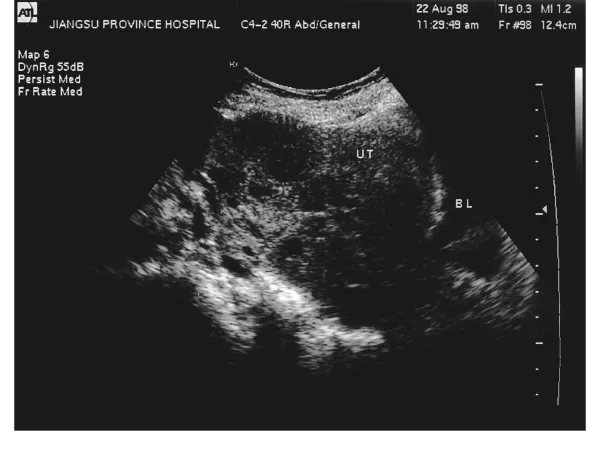

第一,观察等待。这种方式适用于无明显症状或肌瘤较小的患者。医生会定期对肌瘤的生长情况进行监测,建议患者每隔3-6个月复查一次B超。如果肌瘤没有明显增大且没有带来不适,则无需特殊治疗。

第一,定期体检。子宫肌瘤往往在无声无息中出现,定期做妇科检查和B超检查可以帮助早发现、早治疗,对已经有肌瘤的女性也能随时掌握疾病的动态。